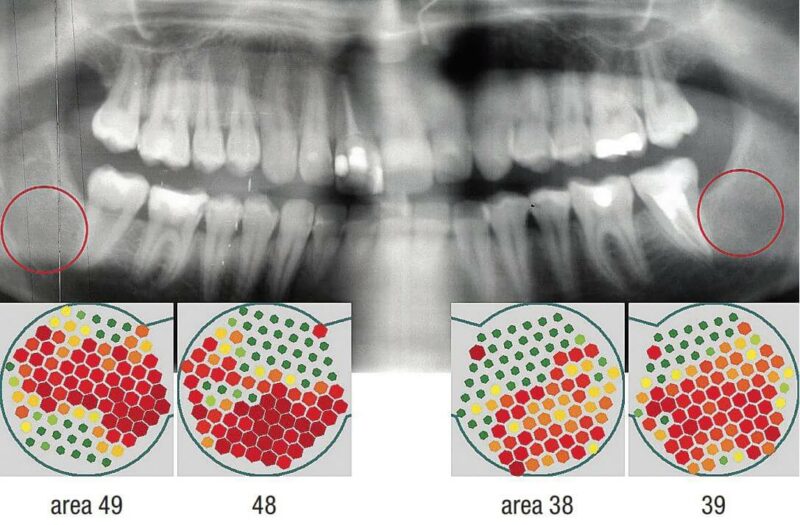

Neuartige Bildgebung im Kieferknochen mit Ultraschall

Measuring bone density by intra-oral ultrasound for secure implant insertion